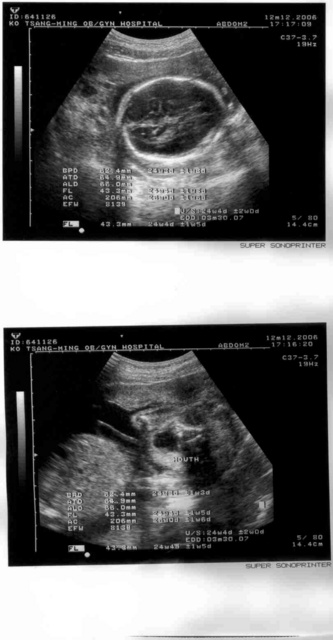

2006.12.12

為了要醫生證明以準備老婆出國的事宜,我們又去做了一次產檢,很可惜的是,我的時間沒辦法配合,不能全程陪同。從超音波照片已經可以很清楚的看到小朋友的輪廓了,現在的體重約八百克,一切正常。

這次小朋友終於沒有躲起來不給看,看到小朋友的嘴巴開開,就好像在說,喔,你抓到我了!另外,又好像是H_L's blog首頁上放的那張畫~~~~~媽媽,你工作太努力了喔,我不要我不要,喔~喔~喔~喔~喔~